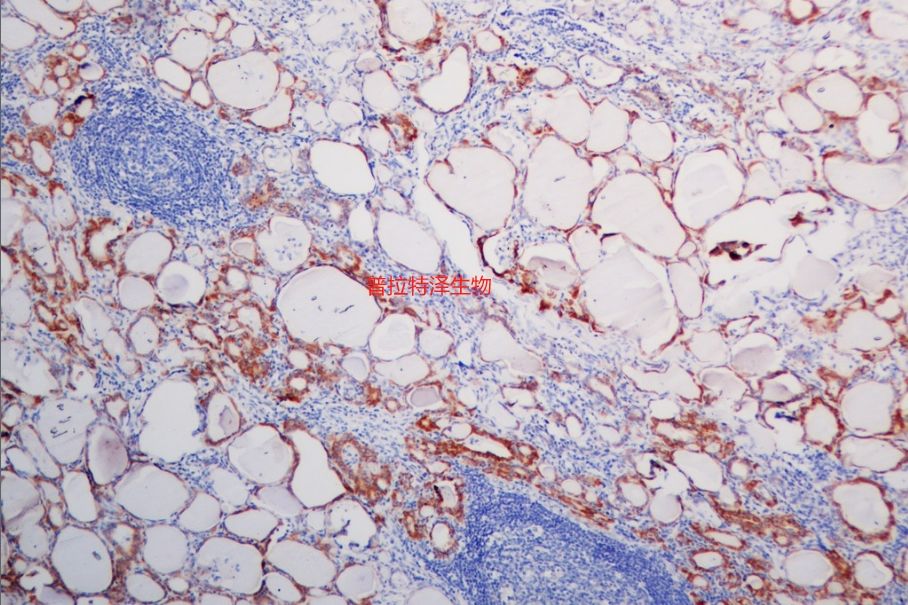

圖二原位雜交